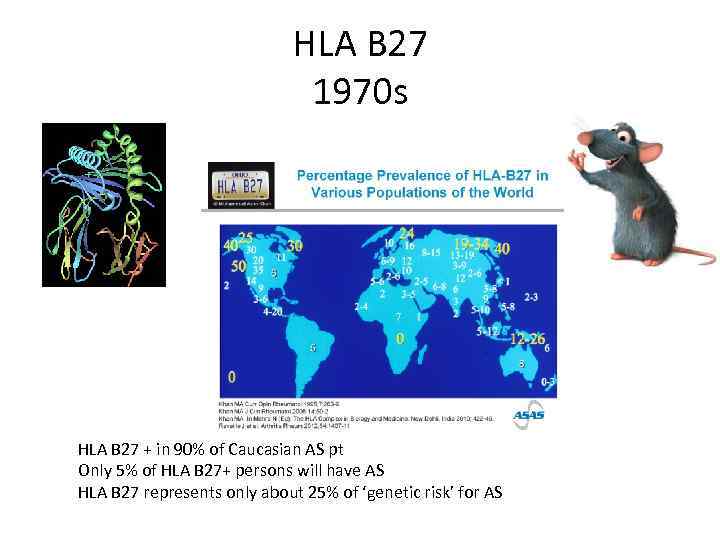

HLA B 27 1970 s HLA B 27 + in 90% of Caucasian AS pt Only 5% of HLA B 27+ persons will have AS HLA B 27 represents only about 25% of ‘genetic risk’ for AS